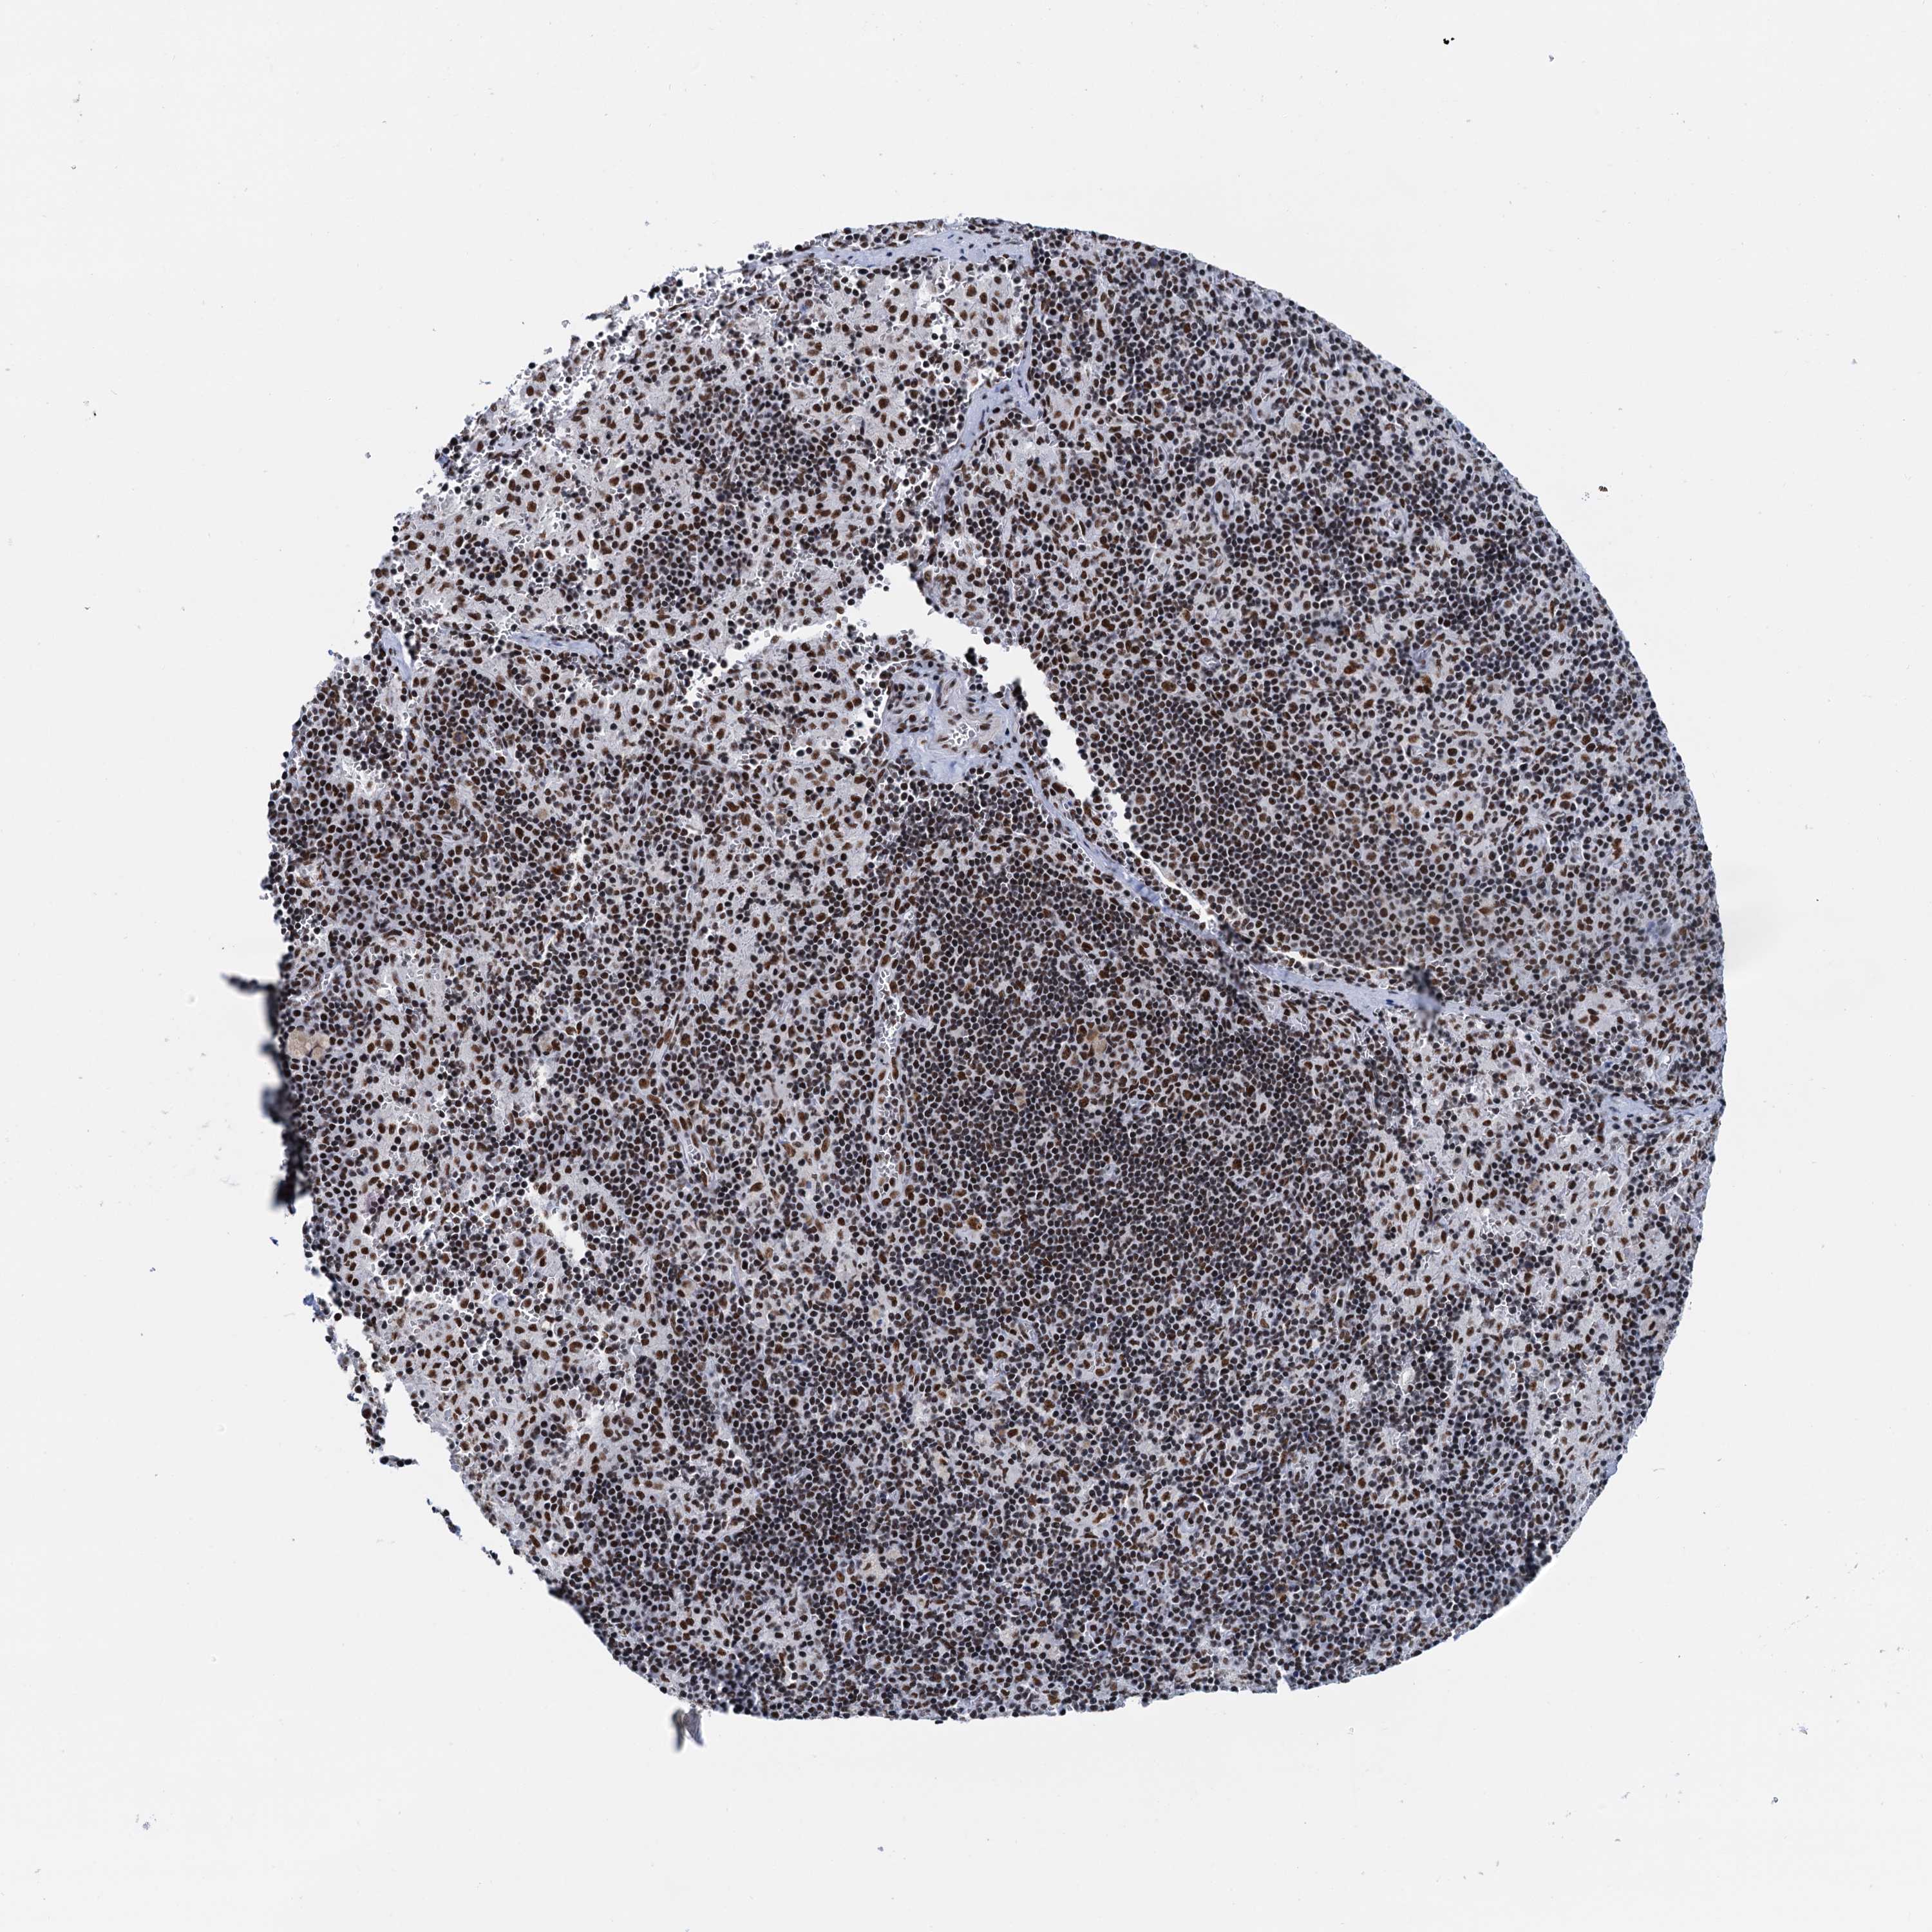

PANCREATIC CANCER - Protein expressioni

A mouse-over function shows sample information and annotation data. Click on an image to view it in a full screen mode. Samples can be filtered based on level of antibody staining by selecting one or several of the following categories: high, medium, low and not detected. The assay and annotation is described here.

Note that samples used for immunohistochemistry by the Human Protein Atlas do not correspond to samples in the TCGA dataset.

Antibody stainingi

Antibody staining in the annotated cell types in the current human tissue is reported as not detected, low, medium, or high, based on conventional immunohistochemistry profiling in selected tissues. This score is based on the combination of the staining intensity and fraction of stained cells.

Each image is clickable and will lead to virtual microscopy that enables deeper exploration of all samples and also displays staining intensity scores, fraction scores and subcellular localization as well as patient and tissue information for each sample.

Antibody HPA040256

Antibody HPA040381

Staining

High

Medium

Low

Not detected

Intensity

Strong

Moderate

Weak

Negative

Quantity

>75%

75%-25%

<25%

None

Location

Nuclear

Cytoplasmic/membranous

Cytoplasmic/membranous,nuclear

Adenocarcinoma, NOS